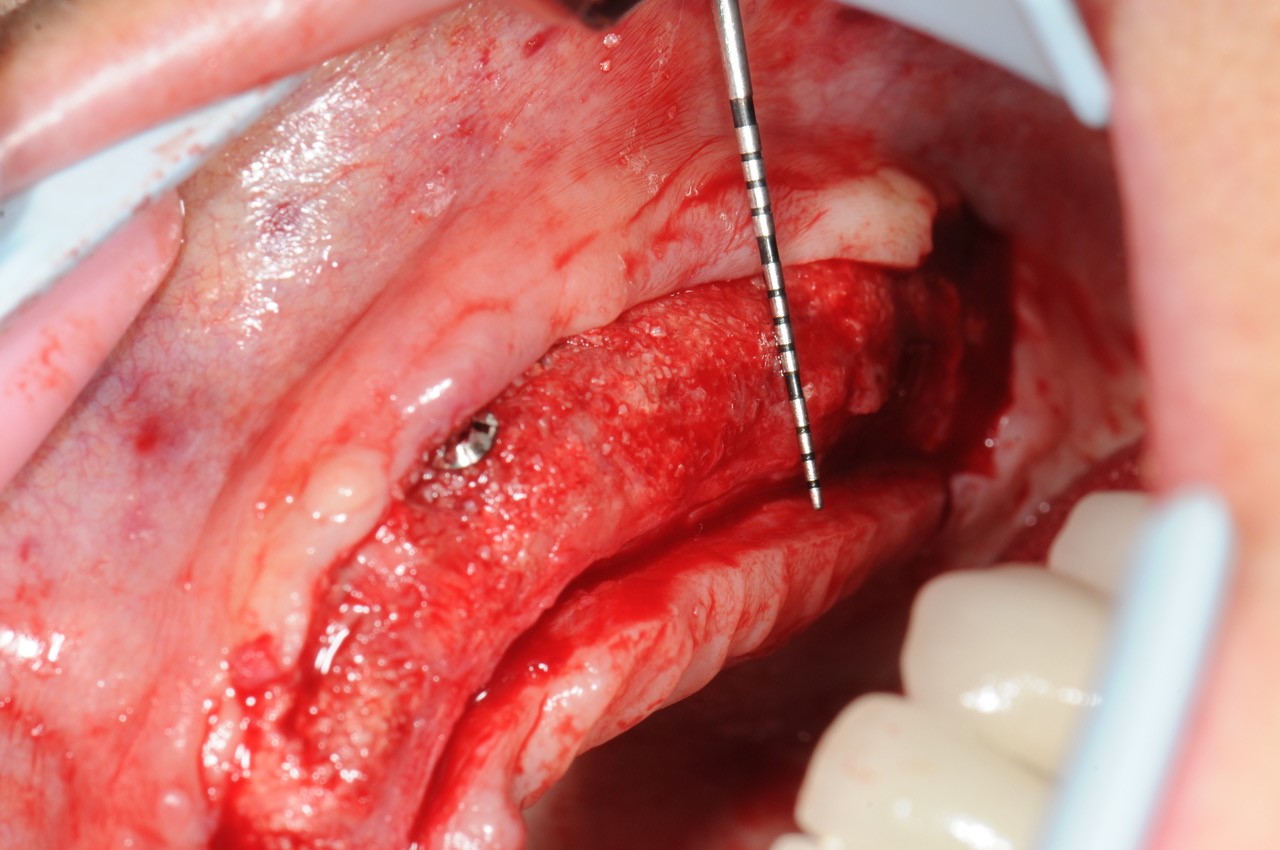

18/21 - 6 months post-op: situation at re-entry shows stable bone

19/21 - Stable bone with approx. 3 mm horizontal bone gain

20/21 - Stable bone with approx. 3 mm horizontal bone gain